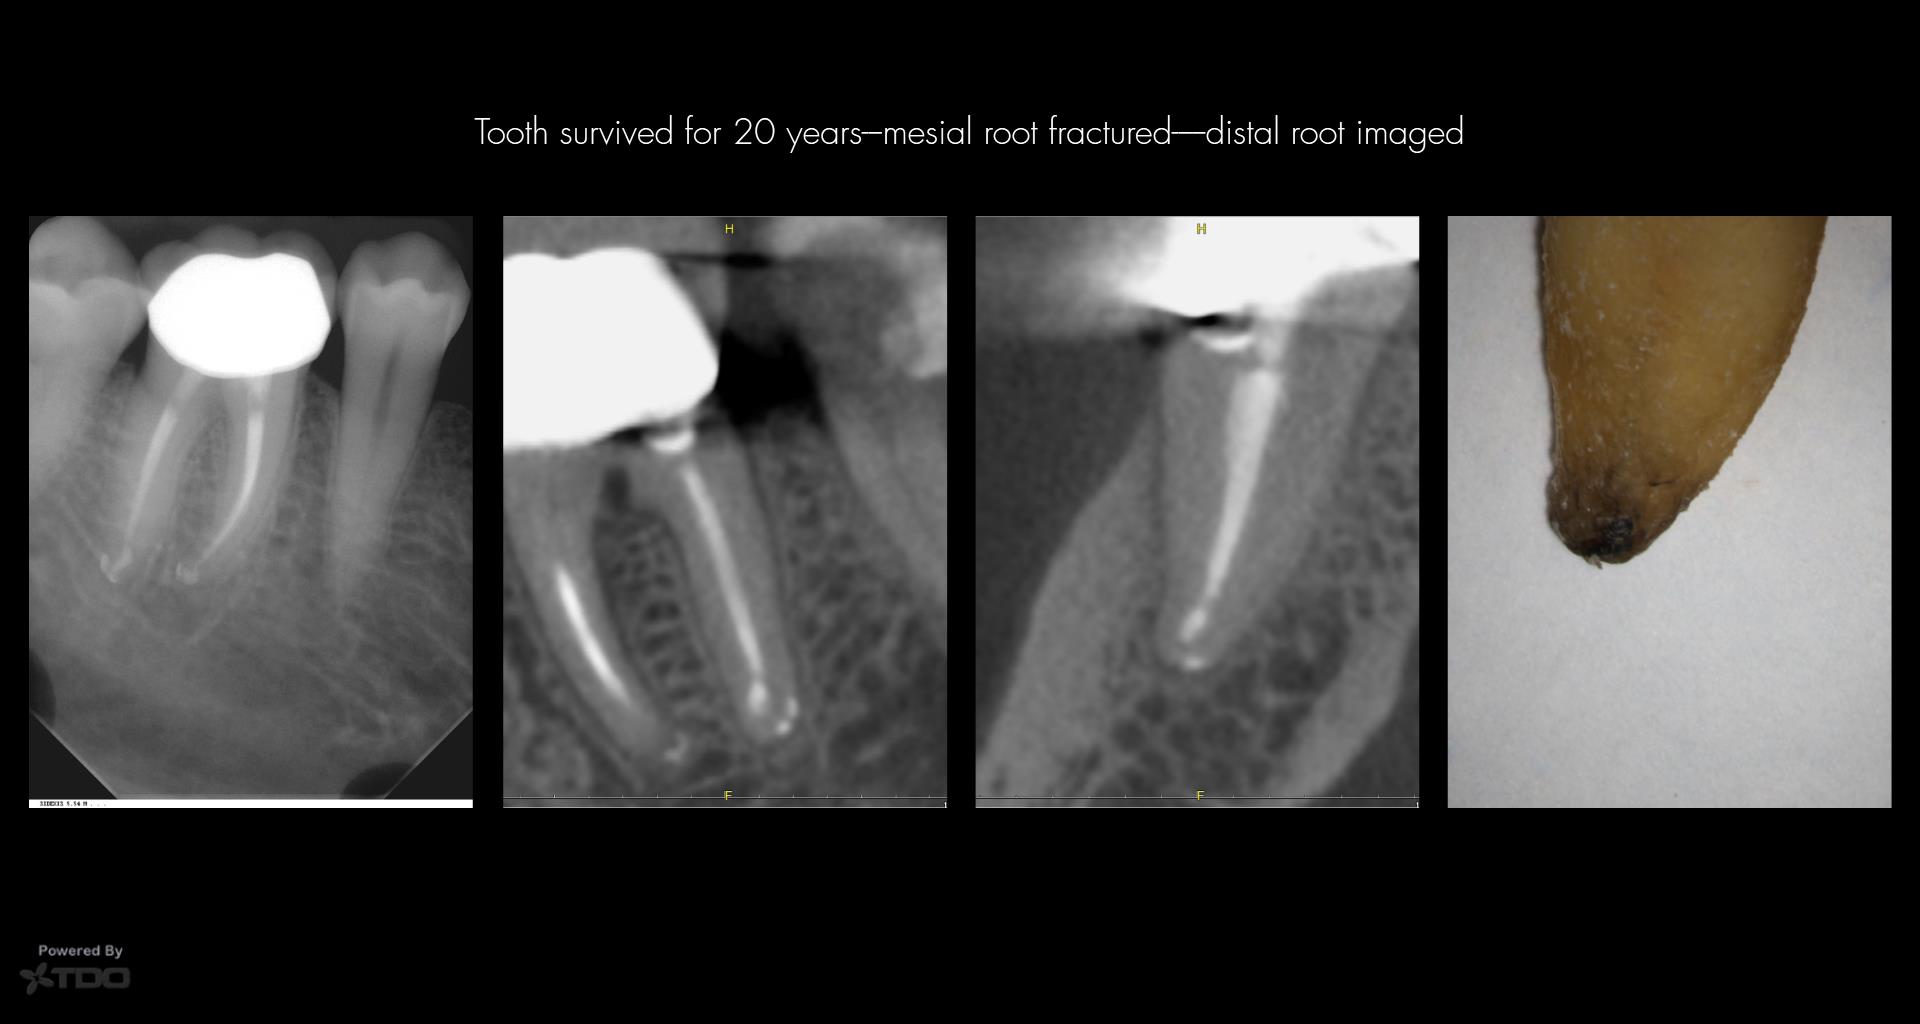

The acknowledgment of uncertainty in identifying sufficient and necessary conditions for diseases highlights the complexity of endodontic cases. Carrs analogy of a house of cards calls for a more nuanced exploration of factors influencing disease outcomes.